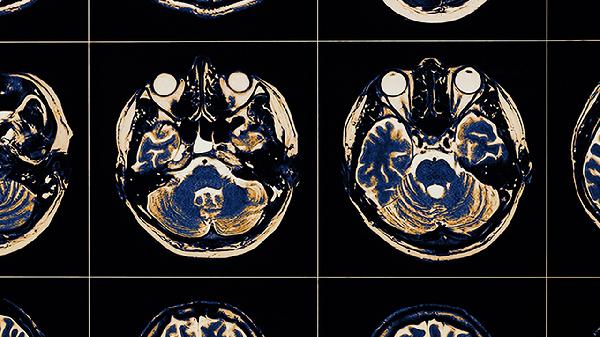

脑血栓取栓术的成功率较高,但具体成功率与患者病情、手术时机等因素有关。脑血栓取栓术是一种通过机械方式将血栓从血管内取出的手术,适用于大血管闭塞导致的急性缺血性脑卒中。

脑血栓取栓术的成功率受多种因素影响。血管再通是衡量手术成功的重要指标,及时进行手术的患者血管再通概率较高。手术时机是关键因素,发病后6小时内进行手术效果较好。患者年龄、基础疾病、血栓位置和大小也会影响手术效果。取栓器械的进步提高了手术成功率,现代取栓设备能够更有效地抓取和清除血栓。术后护理和康复治疗对最终疗效有重要影响。